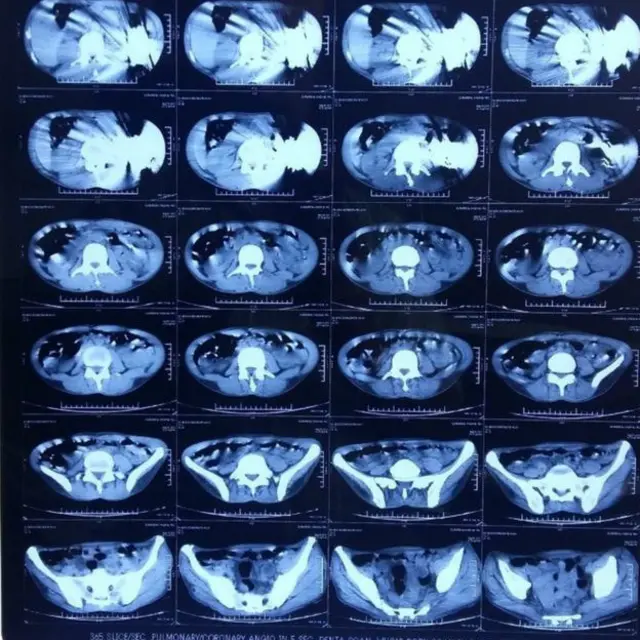

ډاکټرانو د هندي ناروغ له خېټې ۴۰ چړې وایستلې

د هند شمالي امرتسر ښار ډاکټرانو د عملیاتو پرمهال د یوه ناروغ له خېټې ۴۰ چړې ایستلې دي.

ناروغ له دې کبله روغتون ته د درملنې لپاره تللی و، چې ګني د ګېډې شدید درد لري.

یاد ناروغ دغه چړې په تېرو درو میاشتو کې خوړلې وې.

ډاکټر جاتیندر مهوترا بي بي سي ته وویل، ناروغ ډاکټرانو ته دا نه وو ویلي چې ګني چړې یې خوړلې، خو "ازموینو وښوده چې دغه سړي پخپله خوښه دغه چړې خپلې خېټې ته رسولې دي".

دی وايي: "دا جراحي عملیات اسانه کار نه و، موږ باید د ناروغ د ژغورلو او د عملیاتو د بریالیتوب لپاره ښه زیار ایستلی وای".

عملیات د پنځو ډاکټرانو له خوا ترسره شول، خو ناروغ لا تر اوسه سم نه دی رغېدلی.